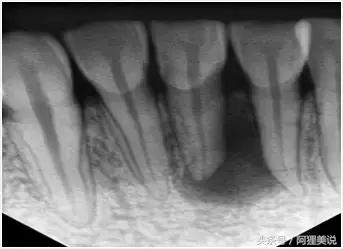

1、术前拍摄X线片

在根管治疗过程中,在根管治疗术前拍X线片,以帮助诊断,了解髓室的位置和根管数目及形态,测量根管工作长度及日后随访和评价疗效提供对比的依据。